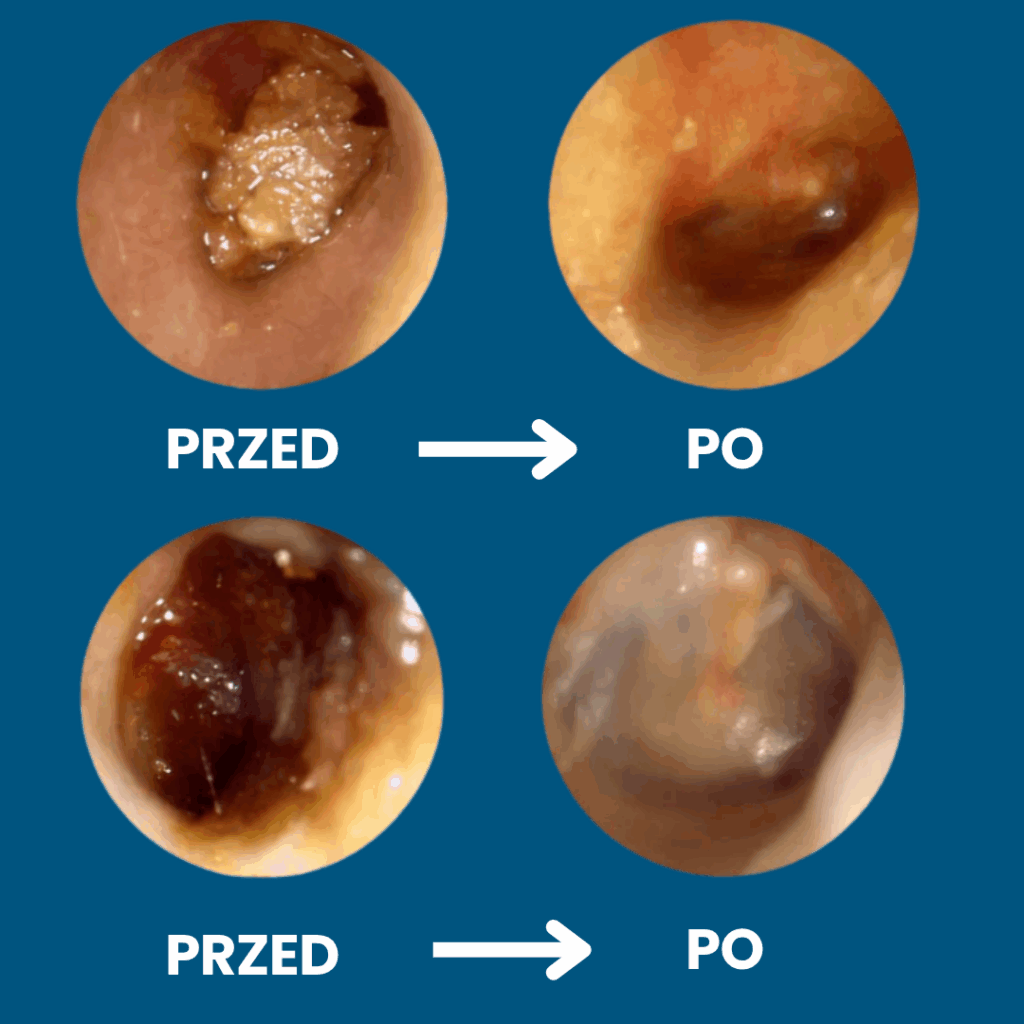

✅ Usuwa zalegającą woskowinę – nie wpycha jej głębiej jak tradycyjne patyczki

Koniec z ryzykiem urazów i infekcji — patyczki często powodują podrażnienia, infekcje i perforację błony bębenkowej. Pełna kontrola dzięki obrazowi HD 1080p — widzisz woskowinę i swobodnie ją usuwasz, zamiast ją wpychać.

Pełna kontrola dzięki obrazowi HD 1080p — widzisz woskowinę i swobodnie ją usuwasz, zamiast ją wpychać. Miękkie silikonowe końcówki zamiast patyczków — precyzyjnie usuwa woskowinę, bez ryzyka zarysowań i dyskomfortu

Higieniczne i oszczędne — wielorazowe końcówki redukują odpady i koszty wymiennych patyczków. Szybka ulga — natychmiastowy efekt komfortu i czystości uszu bez wizyt u specjalisty.

Szybka ulga — natychmiastowy efekt komfortu i czystości uszu bez wizyt u specjalisty.